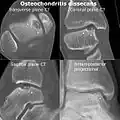

Magnetic resonance imaging (MRI) is useful for staging OCD lesions, evaluating the integrity of the joint surface, and distinguishing normal variants of bone formation from OCD by showing bone and cartilage edema in the area of the irregularity. MRI provides information regarding features of the articular cartilage and bone under the cartilage, including edema, fractures, fluid interfaces, articular surface integrity, and fragment displacement.[37][38] A low T1 and high T2 signal at the fragment interface is seen in active lesions. This indicates an unstable lesion or recent microfractures.[30] While MRI and arthroscopy have a close correlation, X-ray films tend to be less inductive of similar MRI results.[38]

Computed tomography (CT) scans and Technetium-99m bone scans are also sometimes used to monitor the progress of treatment. Unlike plain radiographs (X-rays), CT scans and MRI scans can show the exact location and extent of the lesion.[39] Technetium bone scans can detect regional blood flow and the amount of osseous uptake. Both of these seem to be closely correlated to the potential for healing in the fragment.[40][41]